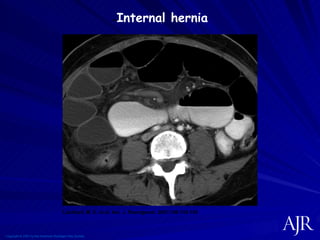

Complications du by pass Malnutrition Carences en micronutriments Gayet Wernicke  Korsakoff Ulcères anastomotiques Sténose Hernie interne

Copyright © 2007 by the American Roentgen Ray Society Lockhart, M. E. et al. Am. J. Roentgenol. 2007;188:745-750 -- Internal hernia